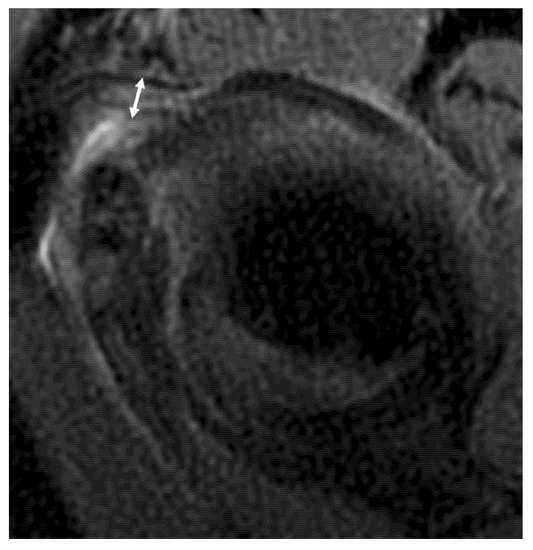

2.5. Image Analysis

- 1: normal homogenous low signal intensity

- 2: partial or foci of signal hyperintensity

- 3: global signal hyperintensity

- 4: linear hyperintensity of the peri-articular soft tissues